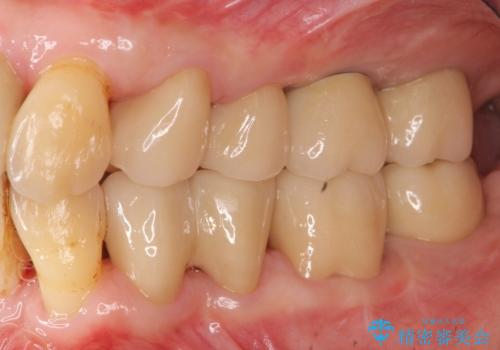

インプラント治療に加え、歯周病に対しての再生治療や歯周ポケットの除去を行う歯周外科、矯正治療、と必要な治療は多岐に渡りましたが、最終的に安定した噛み合わせを得られたとともに、清掃のしやすい口腔内環境を確立できました。